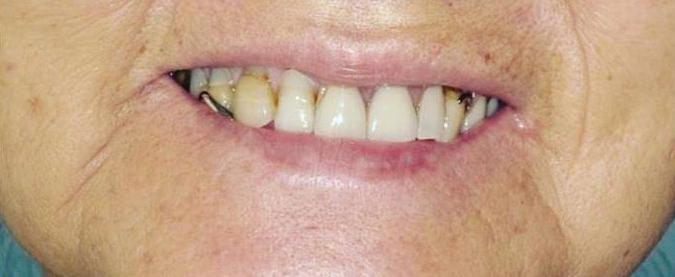

39 | Non-Extraction Orthodontic Treatment | Submitted By Let’s Smile Dental

Can just four implants replace all of the teeth on the top or the bottom of your mouth? Thanks to advances in dental implant technology, that answer is a resounding yes.

Believe it or not, tooth loss is extremely common among adults, especially as we age. In fact, more than 35 million people in America are missing all of their upper and/or lower teeth. Rather than living with the discomfort and hassles of dentures, many people are opting for what is called “all-onfour” dental implant restoration.

Here’s where it gets really interesting: You do not need a dental implant for each and every one of your missing teeth. All you need is four precisely placed implants on the top of your mouth, and four on the bottom, to restore your full smile. That’s the beauty of the all-on-four. And because the implant is made of titanium, it has the unique ability to fuse to living bone and function as part of it. So eventually, the dental implant becomes part of the jawbone and serves as a strong, long-lasting foundation for your new teeth.

Thanks to advances in dental implant technology, just four implants can replace all of the teeth on the top or the bottom of your mouth.

this bone fusion has another important benefit: it prevents future bone loss in the jaw. This helps to maintain a more youthful facial structure – and better oral health. But perhaps the biggest surprise about the all-on-four is how quickly it can transform your life.